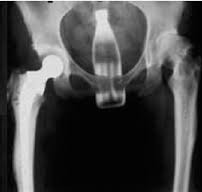

Bomber9: C'era chi le faceva sparire così ...

Margot: bomber la radiografia L hai tenuta per ricordo?